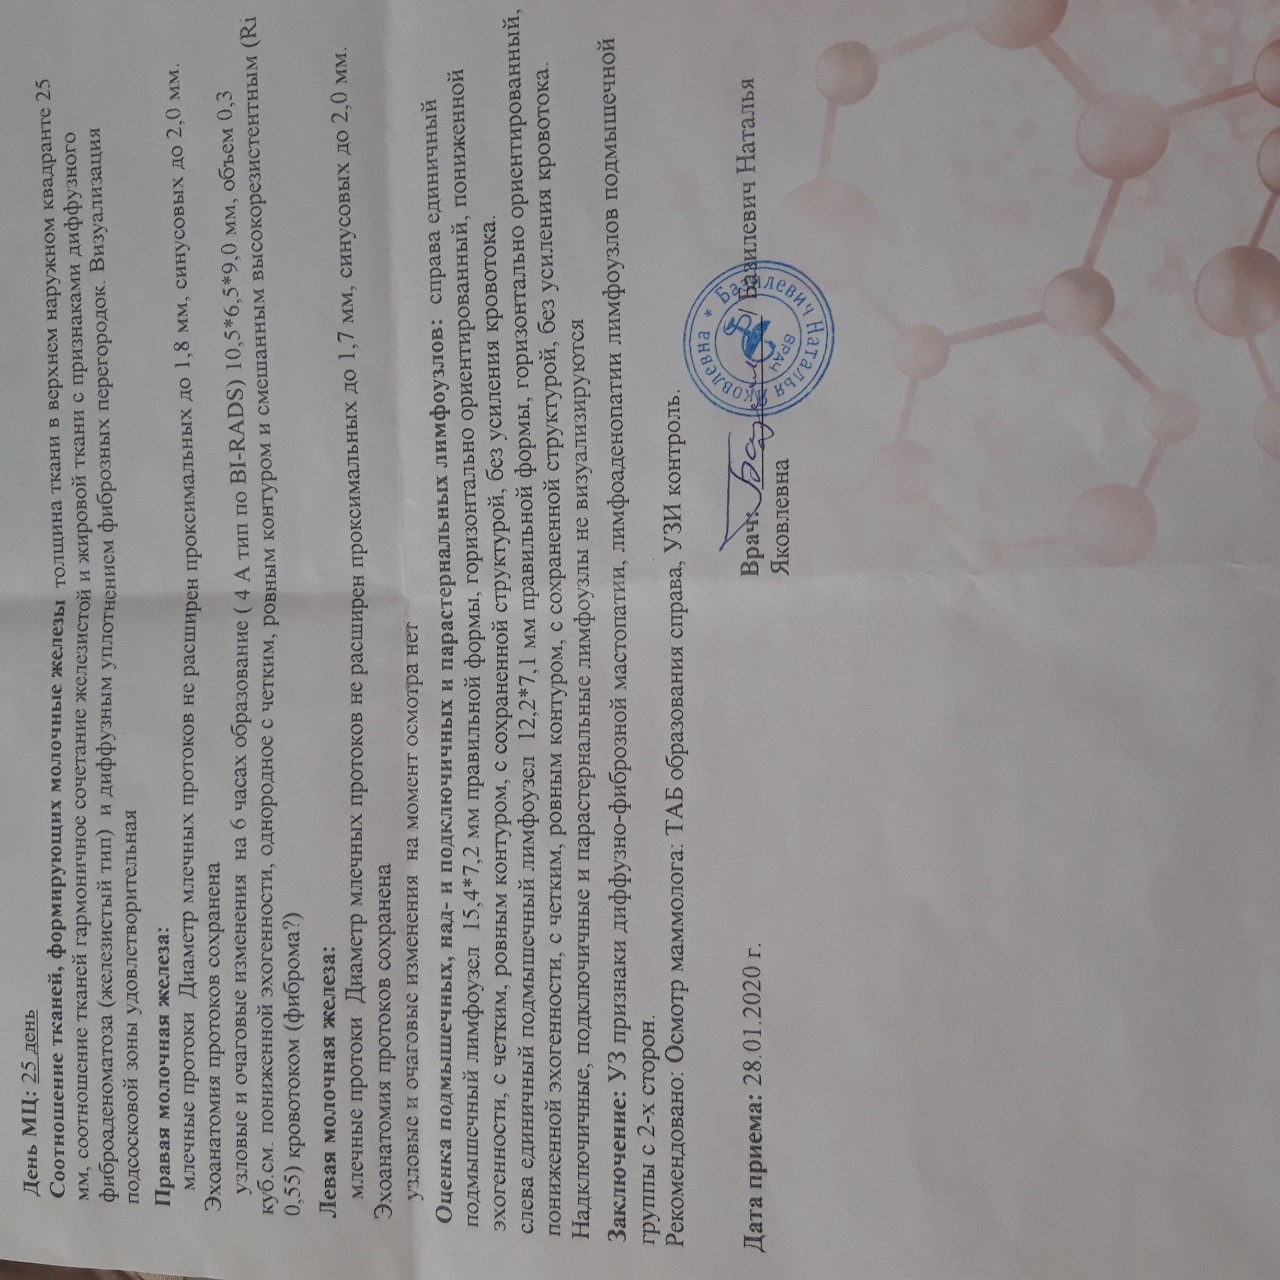

Фиброзно-кистозная мастопатия на УЗИ